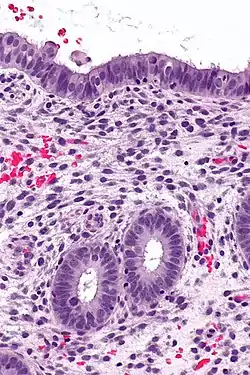

Histology of the most superficial layer of the endometrium, consisting of a simple columnar epithelium. H&E stain

The endometrium consists of a single layer of columnar epithelium plus the stroma on which it rests. The stroma is a layer of connective tissue that varies in thickness according to hormonal influences. In the uterus, simple tubular glands reach from the endometrial surface through to the base of the stroma, which also carries a rich blood supply provided by the spiral arteries. In women of reproductive age, two layers of endometrium can be distinguished. These two layers occur only in the endometrium lining the cavity of the uterus, and not in the lining of the fallopian tubes.[4][5]